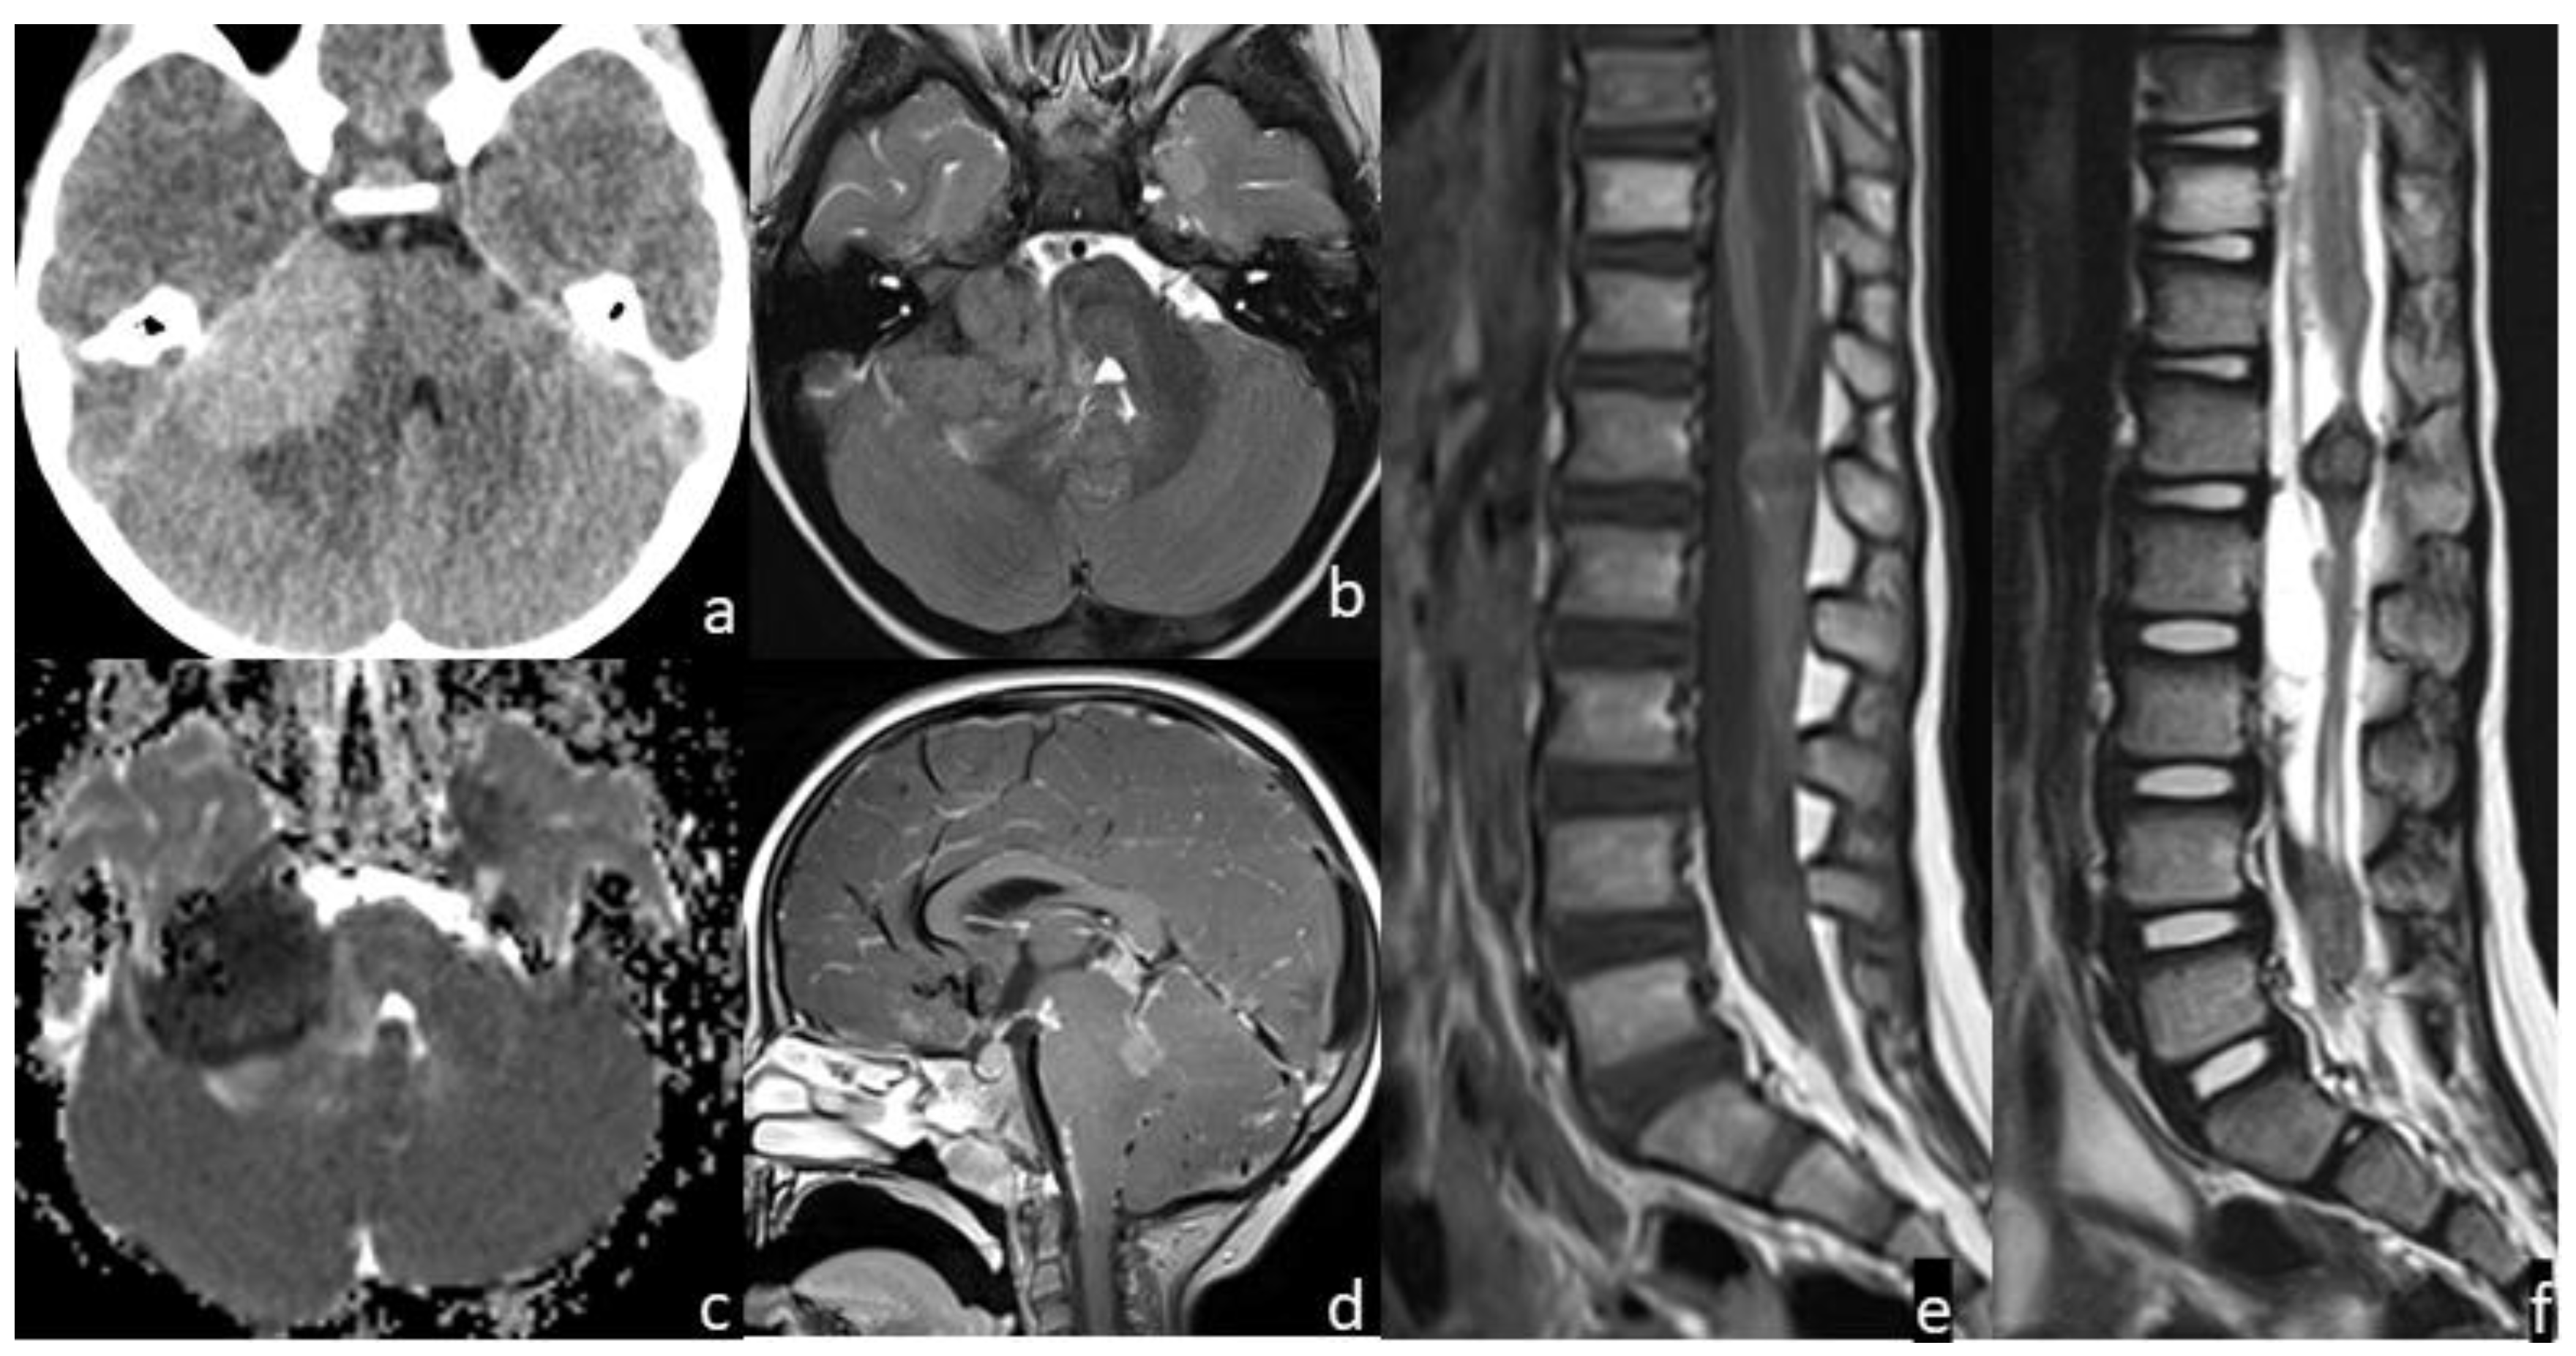

| 4 | diffuse leptomeningeal | supratentorial and infratentorial brain regions; pineal and sellar regions; spine and cauda | >1 | N/A | CT MRI | yes | High | no | yes | yes | restricted | N/A | positive |